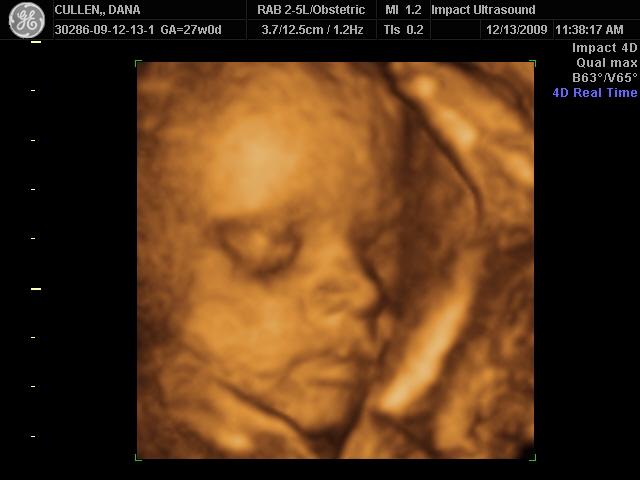

I went to Impact at 27 weeks. Here's DD

Image Attachment(s):